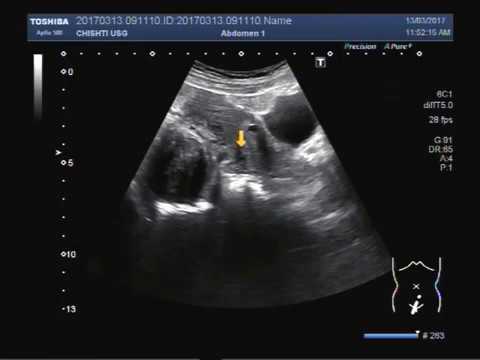

سونوگرافی از طریق واژن روشی برای نشان دادن مایع در پشت رحم است. سیال به خوبی در سونوگرافی نشان داده می شود. در صورتیکه مایعات در داخل کلدوساک یافت شود باعث ایجاد درد می شود. Culdocentesis روش انجام شده برای بررسی سیال غیر طبیعی در منطقه کلدوساک است. قبل از سونوگرافی از طریق واژن، از این روش به طور گسترده استفاده می شد.